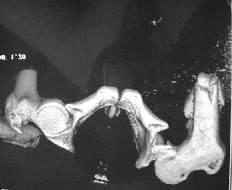

Rayos X.

Fractura subrocantérica de fémur derecho Fielding III.

Fractura oblicua de tercio medio con proximal de tibia izquierda con peroné indemne.

A pesar de que radiológicamente no es visible lesión en cadera se

pide TAC con hallazgo de luxofractura posterior de cadera Thompson Epstein II